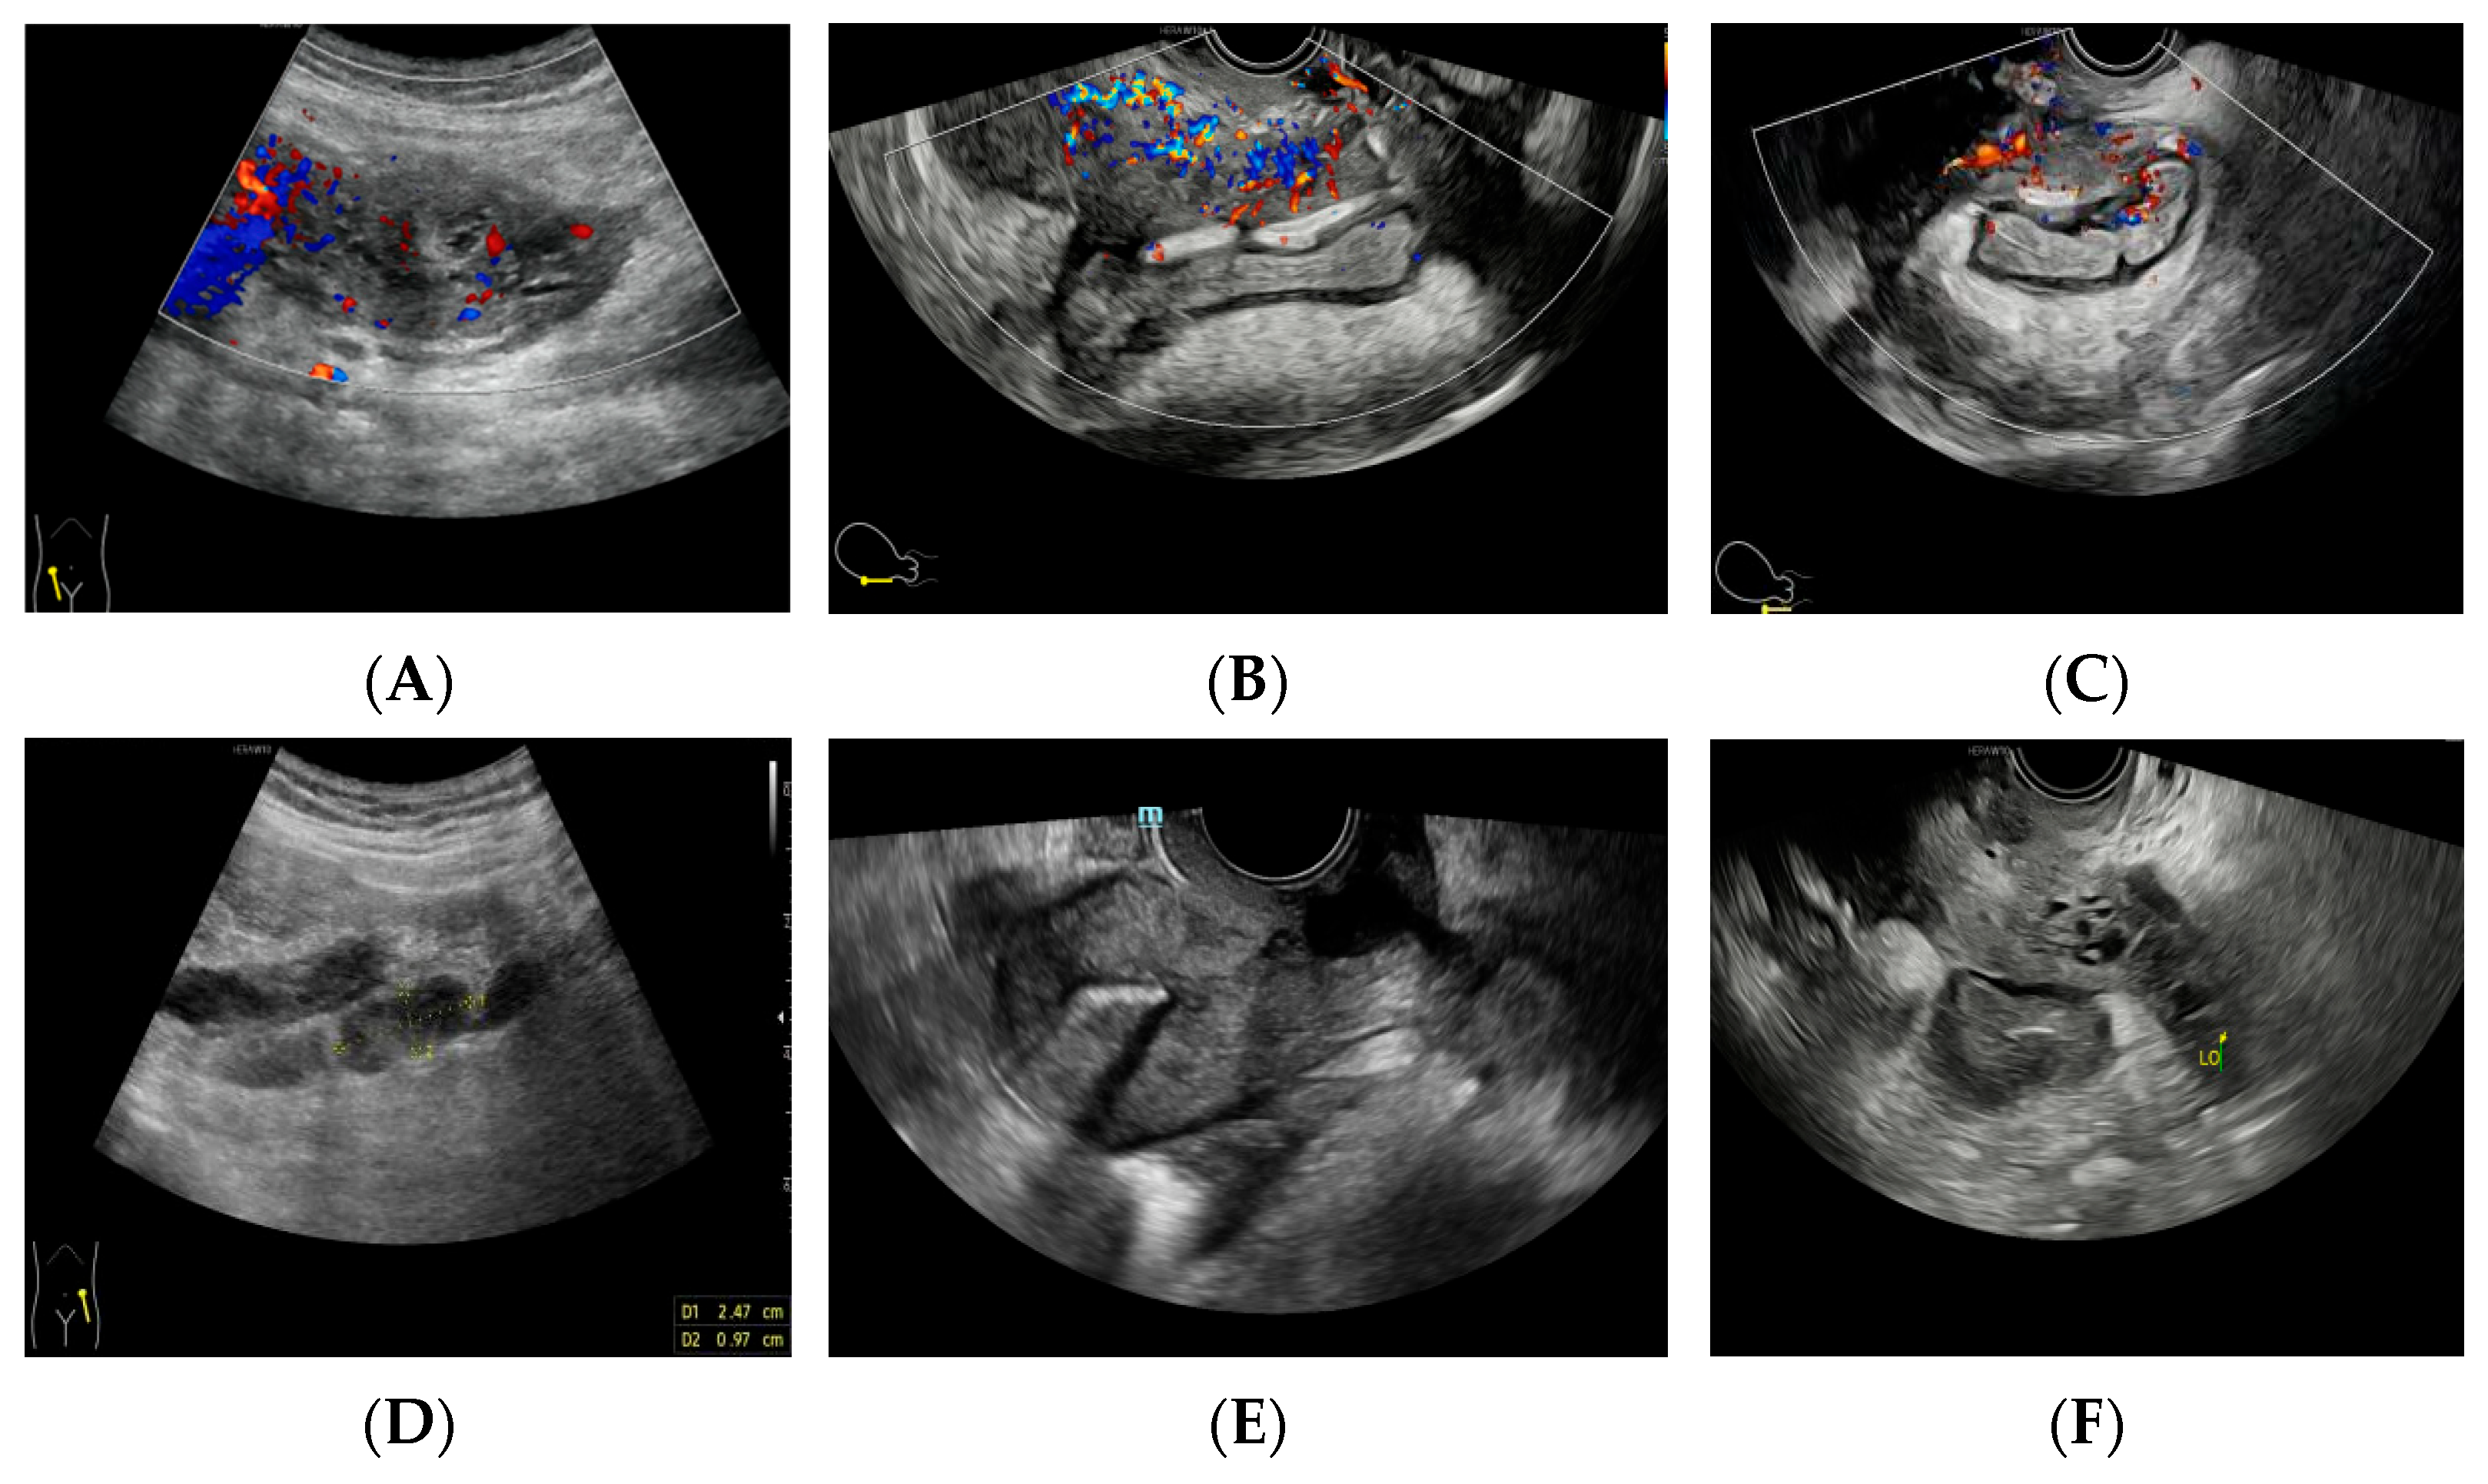

Figure 3.

The preoperative ultrasound detection of pelvic mass: (A) ultrasound detection of a mass of about 8.8 × 4.4 × 4.8 cm in the right adnexa, with abundant blood flow signals, RI: 0.65. (B) The mass is not clearly demarcated from the rectum, sigmoid colon, and sacroiliac ligament. (C) Ultrasound shows thickening and decreased echo of the intestinal wall behind the uterus, with abundant blood flow. (D) Multiple enlarged lymph nodes in the bilateral iliac fossa. (E) A copper-bearing intrauterine contraceptive device, in the normal position. (F) The size and shape of the left ovary are acceptable.

Figure 3.

The preoperative ultrasound detection of pelvic mass: (A) ultrasound detection of a mass of about 8.8 × 4.4 × 4.8 cm in the right adnexa, with abundant blood flow signals, RI: 0.65. (B) The mass is not clearly demarcated from the rectum, sigmoid colon, and sacroiliac ligament. (C) Ultrasound shows thickening and decreased echo of the intestinal wall behind the uterus, with abundant blood flow. (D) Multiple enlarged lymph nodes in the bilateral iliac fossa. (E) A copper-bearing intrauterine contraceptive device, in the normal position. (F) The size and shape of the left ovary are acceptable.